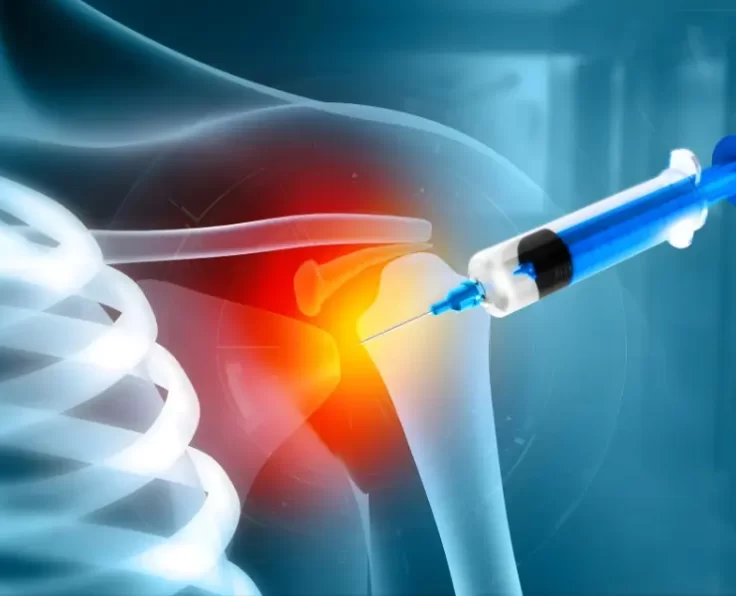

Hydrodilation of Shoulder

Hydro dilation is a treatment for joints that have become painful and stiff as a result of scar tissue build-up. It's most commonly used to…